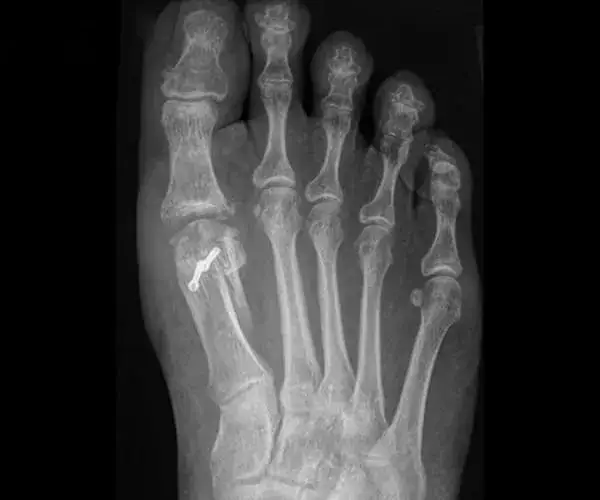

Po około 6 tygodniach, po kontrolnym zdjęciu RTG, które potwierdzi zrost kostny, nadejdzie czas na stopniowe przechodzenie do obuwia codziennego. Pamiętaj, aby na początku wybierać wygodne buty, najlepiej o grubszej, sztywniejszej podeszwie, która zapewni dodatkowe wsparcie i stabilizację dla Twojej stopy. Unikaj butów na obcasie czy z cienką, elastyczną podeszwą.